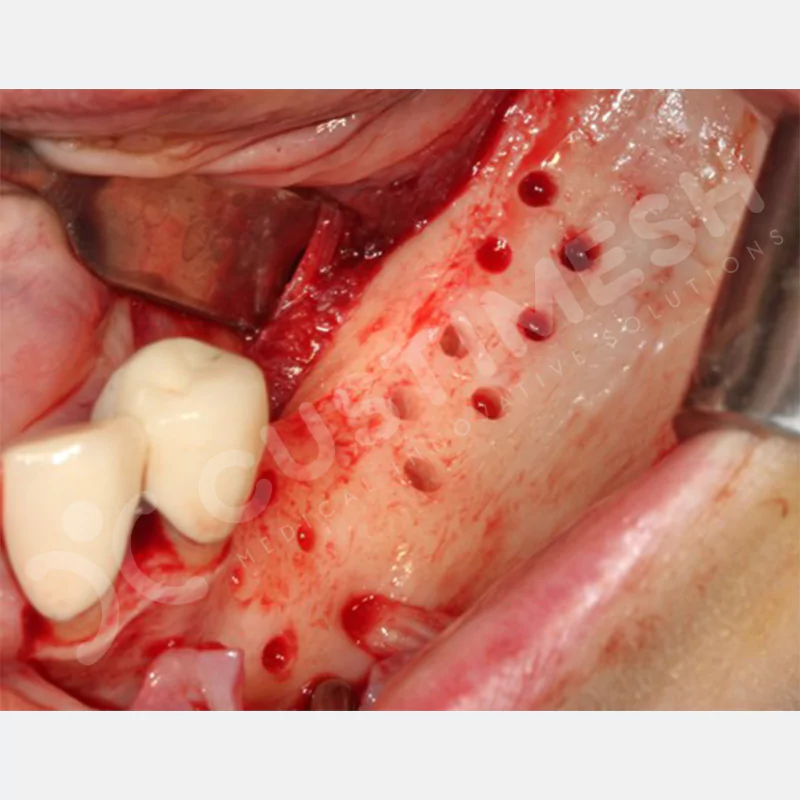

VAKA 3